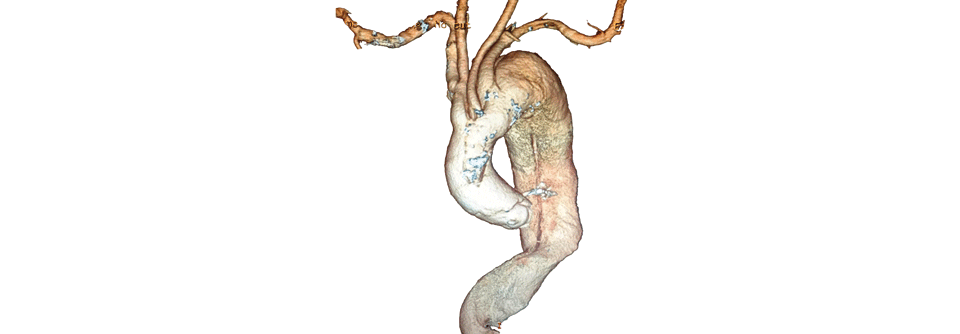

Da der Trend insgesamt Richtung endovaskulärer Aortenreparatur geht, sind die beobachteten Geschlechterunterschiede bei diesem Verfahren bedenklich, so die Autoren. Über die Ursachen der Differenzen könne man derzeit nur spekulieren. Möglicherweise existieren für Frauen einfach keine passenden Stentgrafts, da sich ihre Befunde anatomisch oft komplexer präsentieren – z.B. mit einem kürzeren und schmaleren Aneurysmahals.